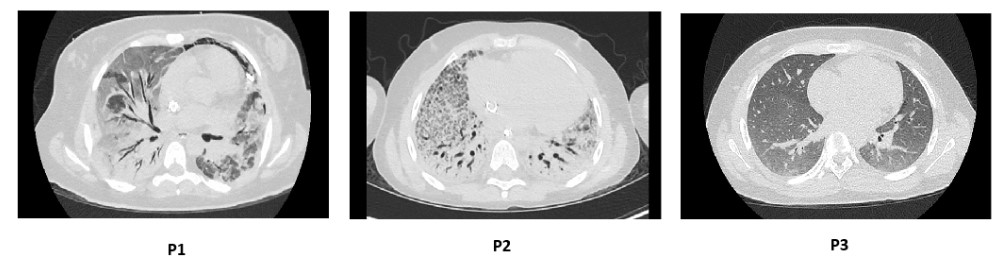

Lung Imaging

High-resolution Computed Tomography of the Chest demonstrates severe ILD in patient P1 and patient P2, and mild early ILD in patient P3.